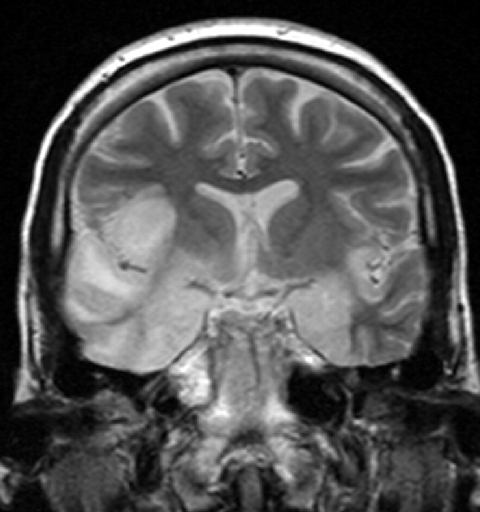

- MR & CT scan diagnosis of HSV encephalitis Medical Image Database